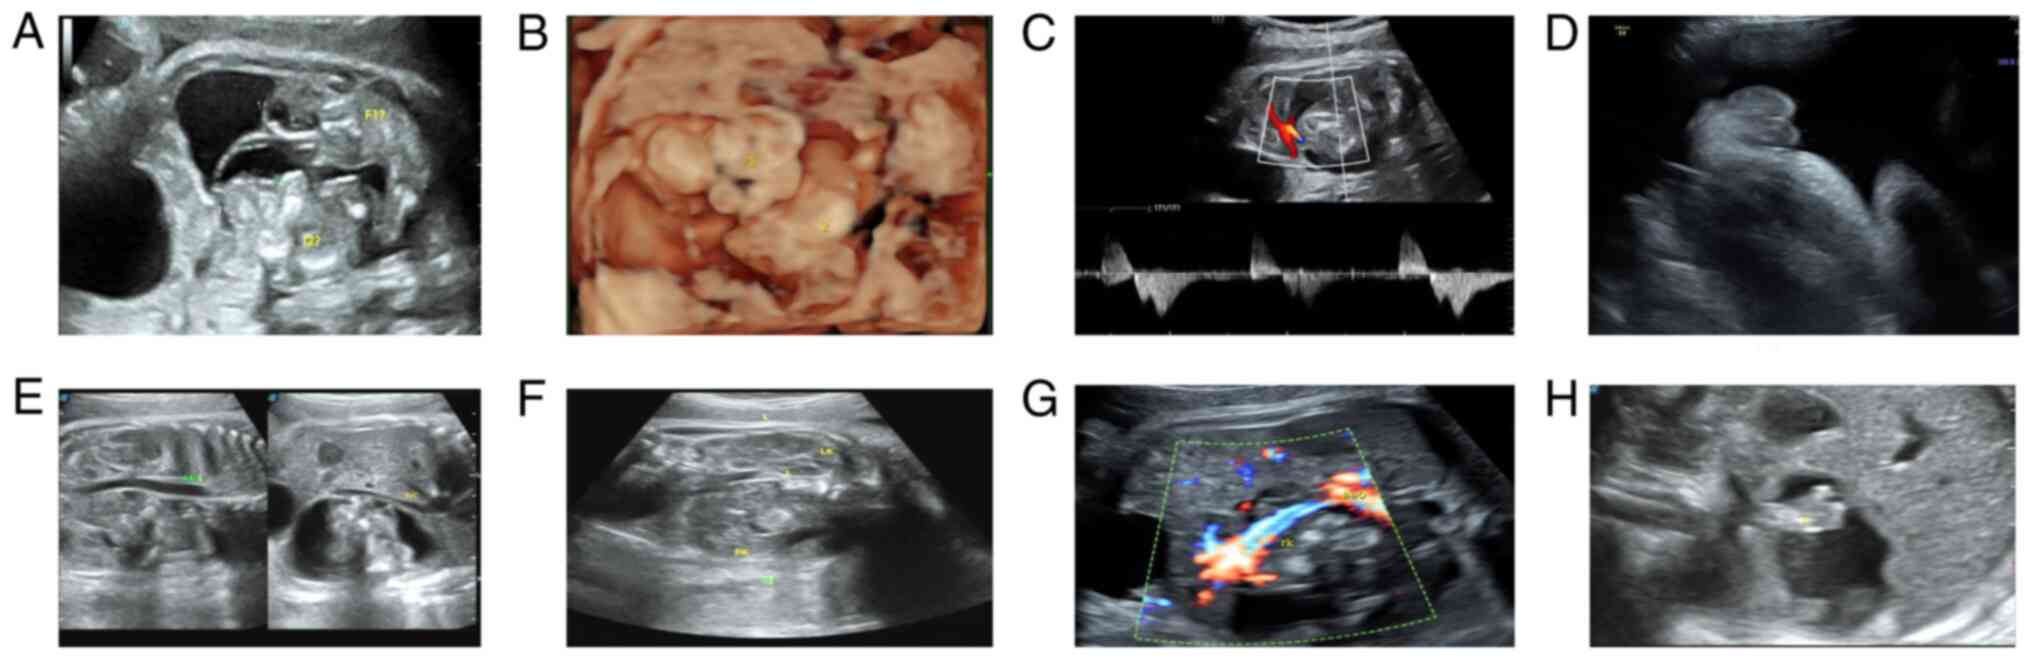

Fetus in fetu (FIF) is a rare anomaly of diamniotic monochorionic twins, where a malformed fetus resides within the body of its twin. Most FIF occurs in the retroperitoneal region around the host spine and appears prenatally as a solid‑cystic mass consisting of fetal‑like structures. Imaging has an important role in the diagnosis of FIF. The present study reported a single case, a 45‑year‑old woman, with a teratoma in a third‑trimester fetus diagnosed after prenatal ultrasonography (US), which showed a mass containing fetus‑like echoes. FIF was considered after the US showed that the mixed solid‑cystic retroperitoneal mass around the vertebral axis of the host fetus consisted of two separate masses, each containing distinct fetal visceral structures. One fetus was acardiac and the other parasitic fetus was visible with a weak heartbeat. Postpartum magnetic resonance imaging and ultrasonography (US) scans of the newborn showed a retroperitoneal cystic space‑occupying mass with distinctive limbs and visceral structures. The pathological examination further confirmed the diagnosis of retroperitoneal FIF. Also, a prenatal US could detect FIF in utero. A cystic‑solid mass containing long bones, vascular pedicles, or visceral structures around the vertebral axis of the host fetus in the US might suggest the possibility of a FIF.

Figure 1